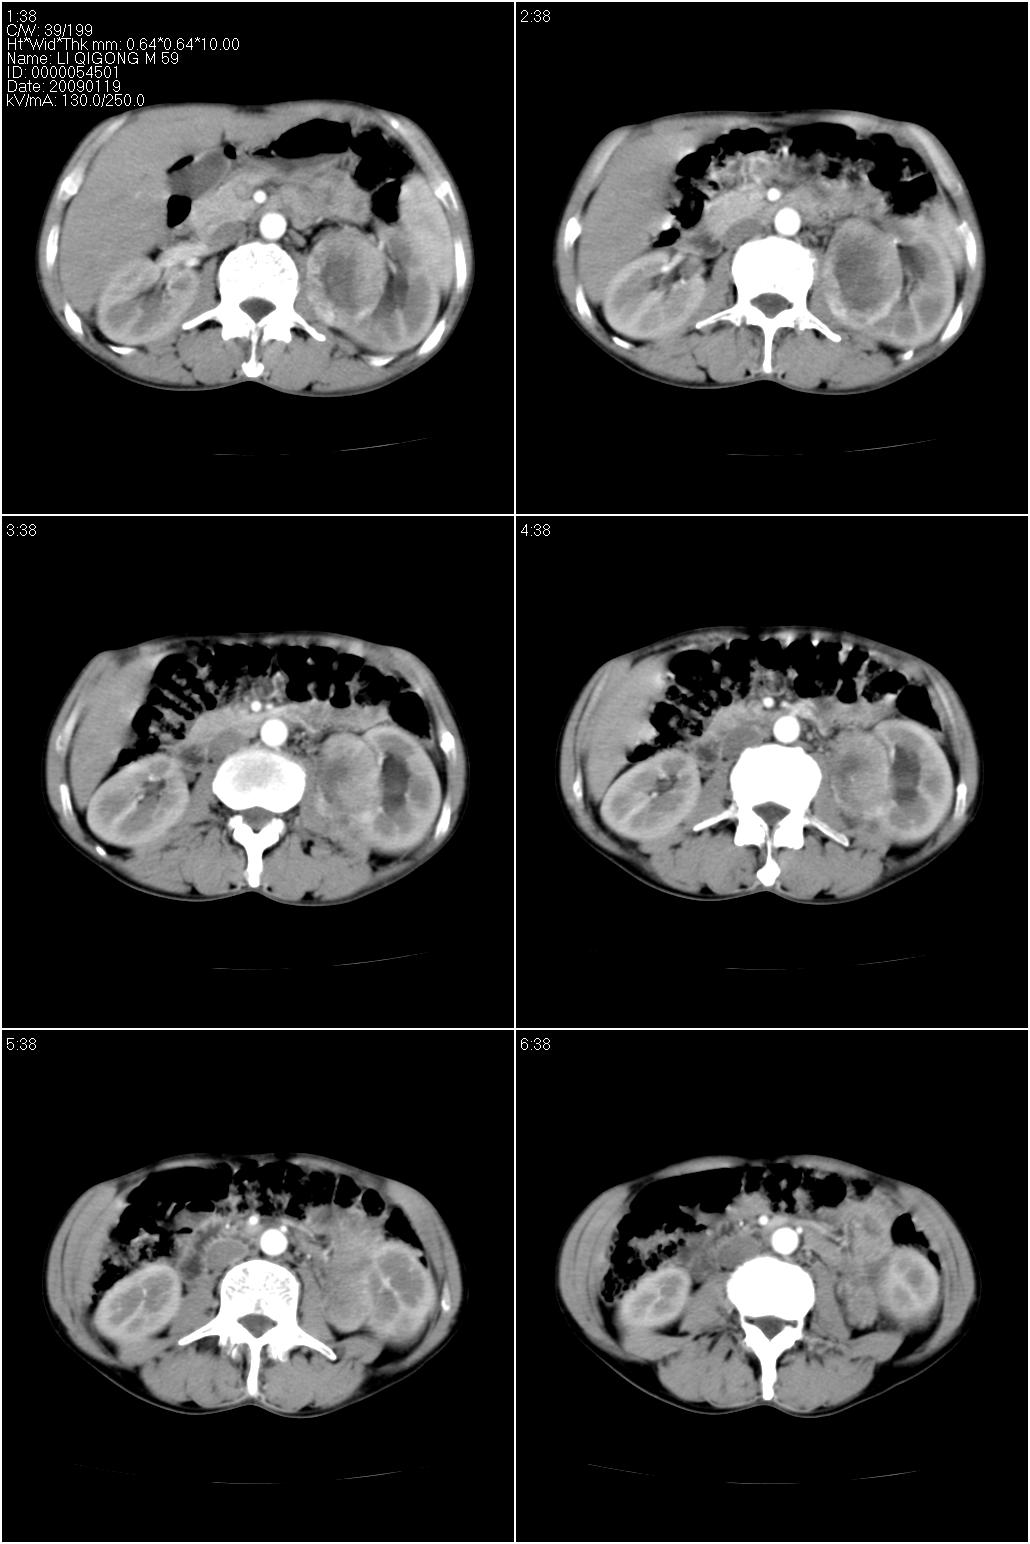

男性,59岁。体检发现左肾占位。自诉无尿血、尿痛。

无痛无血尿,左肾实质占位,有明显强化,中心坏死不规则,应该肾癌无疑。

应该考虑左肾癌并肾盂积水

诊断依据:

1、中老年男性.

2、左肾占位,呈不均匀性强化,中央有无强化的坏死区。

3、左肾门旁有侧枝开放,提示左肾静脉癌栓形成可能。

4、患者自诉无血尿,但不一定镜下无血尿。